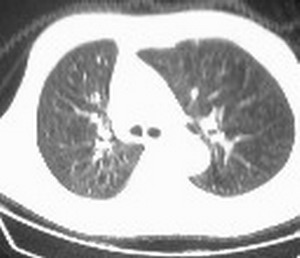

标题: CT6943:[讨论]胸部,M/67Y,体检发现。 [打印本页]

标题: CT6943:[讨论]胸部,M/67Y,体检发现。

ct值约12hu。

ct值约12hu

ct值12,包裹性胸腔积液,

右肺下叶未发育,并包裹性胸腔积液